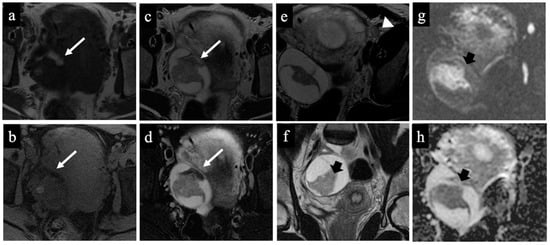

Figure 2. Decidualised endometrioma. MR images of a 34-year-old woman—20 weeks pregnant—with an indeterminate adnexal lesion discovered at the 16-week US. The coronal T2-WI (a), axial T1 (b), T1-WI with fat-saturation (c), T2-WI (d), DWI (e) and ADC-map images (f) show a unilocular cystic right adnexal mass with haemorrhagic content (high signal intensity on the T1-WI, T2-WI, and T1 with fat saturation). This was considered a false positive since both readers misclassified the mass as malignant/score 4 due to the presence of tissue with true diffusion restriction along the lesion’s right lateral wall (arrow). Note the gestational sac in the uterine cavity (asterisk).

Figure 3. Borderline mucinous cystadenoma. MR images of a 28-year-old woman—17 weeks pregnant—with an indeterminate adnexal lesion discovered at the first-trimester US. The sagittal (a), coronal (b), and axial T2-WIs (c), T1-WI with fat-saturation (d), DWI (e) and ADC-map images (f) show a multilocular cystic left adnexal mass with different signal intensities within the loculi. Both readers considered this lesion as benign/score 3 (probable mucinous cystadenoma) because no solid tissue was found (false negative).

Figure 4. Dermoid cyst. MR images of a 32-year-old woman with an indeterminate adnexal lesion discovered at the first-trimester US. The axial T1-WI (a), T1-WI with fat-saturation (b), T2-WI (c,e), T2-WI with fat-saturation (d), coronal T2-WI (f), axial DWI (g) and ADC-map images (f) show a complex right adnexal lesion with fluid and fatty content. Note the drop of the signal of the fatty component, comparing images (a)/(b) and (c)/(d) (long arrow). The expert radiologist correctly classified the mass as benign/score 2 (true negative). The subtle fatty content, the left external iliac node with a short axis of 10 mm (arrowhead in image (e)), and the presence of tissue with true diffusion restriction within the mass (short arrow in images (fh)), tricked the non-expert radiologist who classified it as malignant/score 5 (false positive).